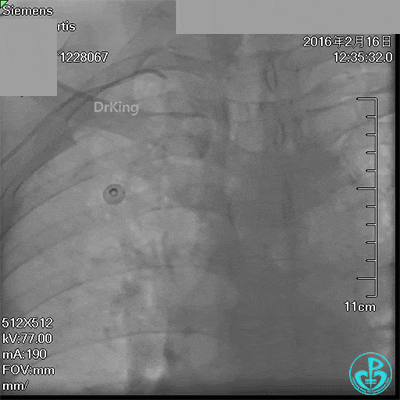

急诊术中导丝在锁骨下通过困难,曾在局部推注造影剂造影,回顾造影结果发现局部小血管破裂造影剂渗漏。